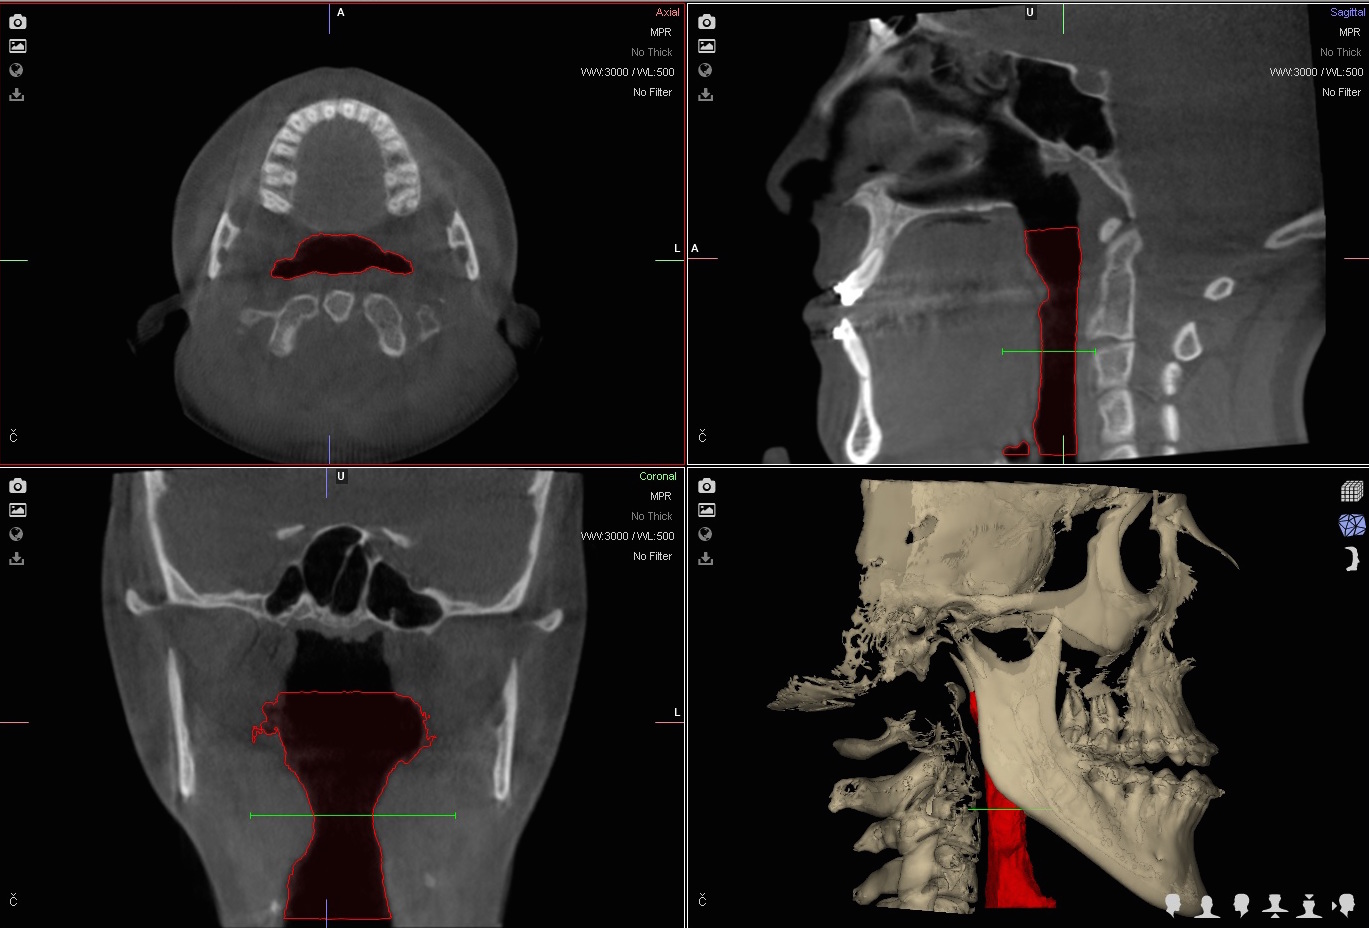

Trójwymiarowe planowanie leczenia wad zgryzu

Nie wyobrażamy sobie planowania operacji wady zgyzu inaczej niż w środowisku 3D.

Jedną z najistotniejszych części leczenia interdyscyplinarnego pacjentów z wadami szkieletowymi jest właściwe zaplanowanie całego procesu leczenia zarówno pod względem przesunięć zębów jak też zmian w układzie kostnym.

Szkielet czaszki twarzowej jest bryłą przestrzenną i rozpatrywanie jego nieprawidłowości w układzie trójwymiarowym pozwala na prawidłowe ich zdiagnozowanie a tym samym na optymalne zaplanowanie przesunięć kostnych, uzyskanie właściwych proporcji twarzy.

U każdego Pacjenta rozpoczynającego leczenie w naszym Centrum po wykonaniu badań diagnostycznych przeprowadzamy szczegółowe analizy dotyczące wzajemnych relacji kostnych w obrębie twarzy, ustawienia zębów, projekcji tkanek miękkich i estetyki twarzy.

Następnie rekomendujemy lub wdrażamy postępowanie ortodontyczne. Po jego zakończeniu przystępujemy ponownie do analiz wszystkich parametrów w obrębie twarzy i przygotowujemy plan leczenia chirurgicznego obejmjący przesunięcia kostne z zakresie układu szkieletowego z uwględnieniem koncepcji FAB.

Docelowo efektem jest wydruk szablonów chirurgicznych na drukarce 3D.

W trakcie planowania powstają rownież symulacje efektów leczenia (symulacje a więc nie gwarantowany efekt), które są przedstawiane pacjentowi przed wykonaniem zabiegu.